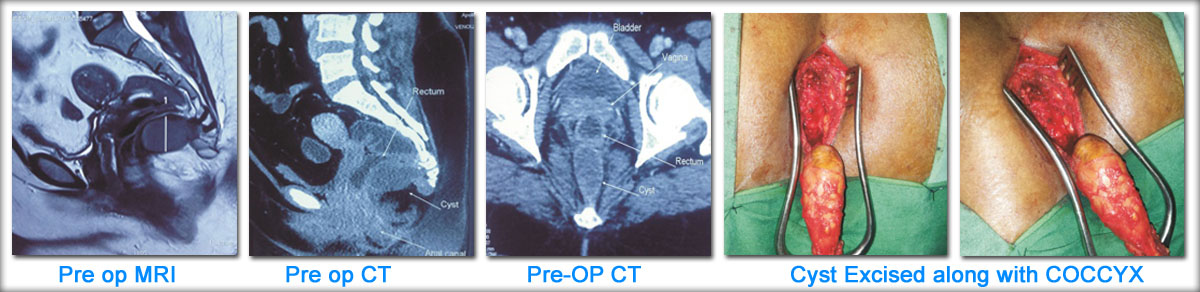

Case Example - Tail Gut Cyst

54 yr old women with pain in tail bone on sitting was found to have cystic tumour attached to coccyx. Coccygectomy with tumour excision was done and patient got relieved of symptoms.